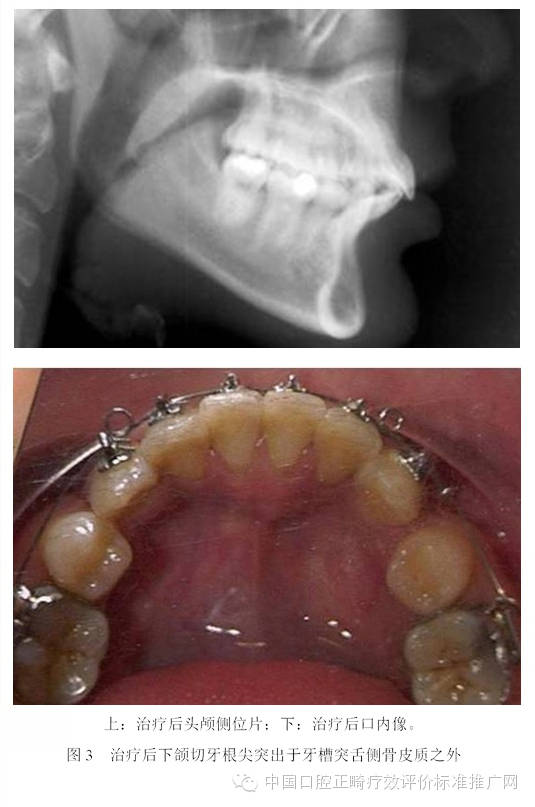

為了避免支抗的丟失,正畸醫(yī)師終于發(fā)現(xiàn)了最強(qiáng)的支抗裝置---金屬種植釘支抗。在用支抗磨牙拉前突的切牙時(shí),切牙牙根在接觸腭側(cè)骨皮質(zhì)后移動(dòng)的阻力會(huì)非常大,于是支抗磨牙會(huì)前移而最終關(guān)閉間隙;但當(dāng)改用種植釘支抗拉前牙時(shí),由于種植釘是絕對(duì)支抗,在矯治力作用下幾乎不動(dòng)[6],因此當(dāng)切牙牙根與腭側(cè)骨皮質(zhì)接觸后,種植釘仍然不會(huì)作任何讓步,那么進(jìn)一步對(duì)抗的結(jié)果會(huì)怎么樣?理想的結(jié)果是腭側(cè)骨皮質(zhì)的牙根一側(cè)發(fā)生骨吸收,而舌側(cè)骨板發(fā)生骨沉積,牙齒帶著牙槽骨一起向腭側(cè)移動(dòng)。問(wèn)題是骨吸收與骨沉積的數(shù)量相等嗎?速度一致嗎?為了回答這個(gè)問(wèn)題,筆者[7]10年前作過(guò)一個(gè)上頜切牙內(nèi)收對(duì)其前后方牙槽骨改建的探索性研究。該研究選擇55例平均年齡為13.3歲的青少年錯(cuò)合患者為研究對(duì)象,采用拔除上下頜第一前磨牙進(jìn)行矯治,平均保持時(shí)間為3年。通過(guò)測(cè)量上切牙阻力中心前方及后方牙槽骨在治療前、治療后及保持后的骨量變化,以及牙槽突總厚度在上述3個(gè)時(shí)間點(diǎn)的變化,結(jié)果發(fā)現(xiàn):上切牙阻力中心在治療后向腭側(cè)平均移動(dòng)了1.8mm (P<0.001);與阻力中心水平的唇側(cè)牙槽骨厚度增加了0.2mm (P<0.01),腭側(cè)牙槽骨厚度減小了0.8mm (P<0.001);隨訪(fǎng)期上切牙阻力中心向唇向復(fù)發(fā)了0.8mm (P<0.01),與阻力中心水平的唇側(cè)牙槽骨厚度相應(yīng)減小了0.2mm (P<0.05),但腭側(cè)牙槽骨厚度卻并沒(méi)有明顯的增加;與上切牙阻力中心水平的牙槽突總厚度基本保持在治療后的水平。由此可見(jiàn),在牙齒移動(dòng)的過(guò)程中,牙槽骨的生物學(xué)改建是以骨吸收為主,骨增生十分有限,即使是保持3年以后,骨增生的量也未達(dá)到其吸收的量。雖然這只是個(gè)初淺的臨床研究,尚有待基礎(chǔ)研究去證實(shí),但它卻部分解釋了正畸臨床上在對(duì)骨性錯(cuò)合患者進(jìn)行牙代償性矯治時(shí),會(huì)出現(xiàn)牙槽骨吸收、裂隙、穿孔,牙齦萎縮或部分根尖移出牙槽骨的現(xiàn)象[8-13]。圖3為1例成人患者在用牙代償性治療方法減少重度深覆蓋深覆合時(shí)出現(xiàn)切牙根尖從舌側(cè)移出牙槽骨的X線(xiàn)影像;圖4為1例采用種植釘支抗大量?jī)?nèi)收上下頜前牙的患者,治療后牙根移出至牙槽突之外的錐形束CT影像。

目前尚不清楚正畸過(guò)程中出現(xiàn)骨開(kāi)窗或骨開(kāi)裂的危害,對(duì)CT影像上牙根突出于骨皮質(zhì)之外多少會(huì)出現(xiàn)有臨床意義的骨開(kāi)窗或骨開(kāi)裂也不得而知,更不清楚由正畸牙移動(dòng)造成的骨開(kāi)窗或骨開(kāi)裂能不能自行修復(fù)。雖然這些問(wèn)題尚無(wú)明確的答案,但是從牙周健康的角度考慮,任何醫(yī)師都沒(méi)有理由相信牙根在牙槽骨之外會(huì)比在它本來(lái)應(yīng)該位于的牙槽突之內(nèi)更加健康。由此可見(jiàn),正畸支抗并非越強(qiáng)越好。70多年以前,正畸學(xué)先驅(qū)Tweed醫(yī)師考慮到牙弓唇頰側(cè)的邊界,提出了拔牙矯治的概念;今天,當(dāng)種植釘支抗風(fēng)靡全球之際,當(dāng)正畸醫(yī)師有能力將前牙無(wú)限內(nèi)收之時(shí),難道不該問(wèn)一句:“牙弓的舌側(cè)有沒(méi)有邊界?”